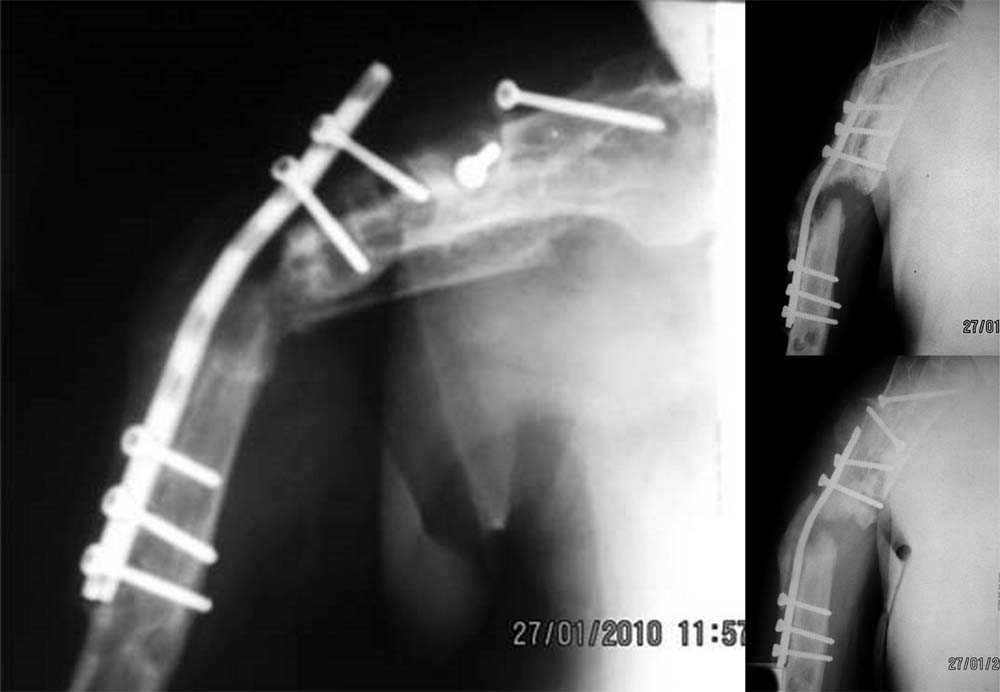

Ложный сустав плечевой кости

Уважаемые коллеги! Имеется случай ложного сустава плечевой кости с дефектом костной ткани, последствиями остеосинтеза.

Больной Г., 54 - х лет, получил закрытый перелом правой плечевой кости 2 года назад. Травма непрямая. Лечился в профильном отделении. Оперирован дважды - первый раз закрытый блокируемый остеосинтез штифтом Ключевского с просверленными отверстиями для блокировки. Сращения не достигнуто, остеосинтез несостоятелен, фиксатор удален. Оперирован повторно - выполнена открытая репозиция, накостный остеосинтез. К сожалению, какого - либо документального материала о лечении на предыдущем этапе не сохранилось.

Локально: множественные послеоперационные рубцы по всему плечу, состояние их удовлетворительное, признаков воспаления нет. Визуально варусная деформация плеча. Отведение в плечевом суставе до 60 град. В с\з - в\з плеча патологическая подвижность, при усилении деформации пальпаторно определяется верхний конец пластины. Болевой синдром не выражен. В анамнезе после второй операции - нейропатия лучевого нерва. В настоящее время клиники нет.